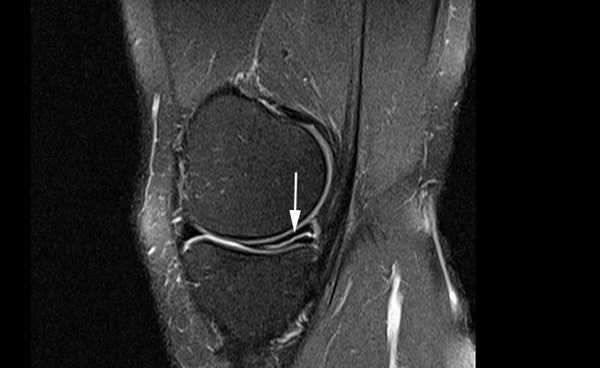

Разрыв заднего рога медиального мениска на снимке МРТ

Лечение зависит от степени поражения. При I и II специалисты рекомендуют консервативные методы и покой, III стадия требует хирургического вмешательства.

Признаком повреждения мениска служит наличие линейного гиперинтенсивного очага на Т2-взвешенных изображениях. Участок сообщается с суставной поверхностью хряща, линию разрыва прослеживают на двух и более сканируемых срезах. При этом наблюдают деформацию и фрагментацию пластины.

Томограмма коленного сустава при радиальном разрыве мениска (указан стрелкой)

В зависимости от степени повреждения на снимках МРТ в режиме Т2 видны:

- очаг повышения интенсивности сигнала шаровидной формы, не связанный с поверхностью мениска (I стадия);

- светлый участок линейной формы, не затрагивающий хрящевой край (II стадия);

- повышение интенсивности сигнала распространяется на одну (III a) или обе (III b стадия) суставные поверхности пластины.